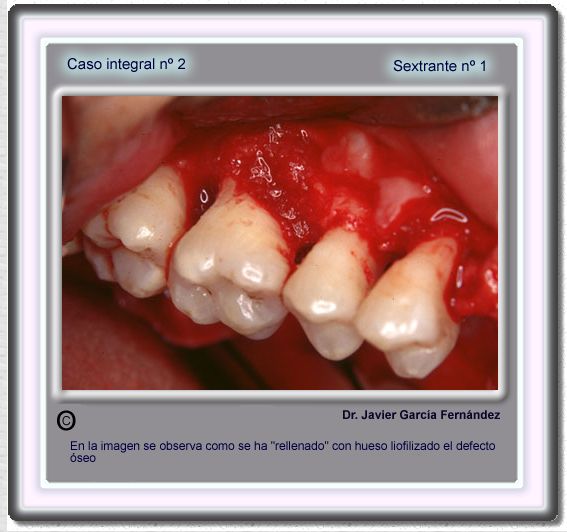

image 28